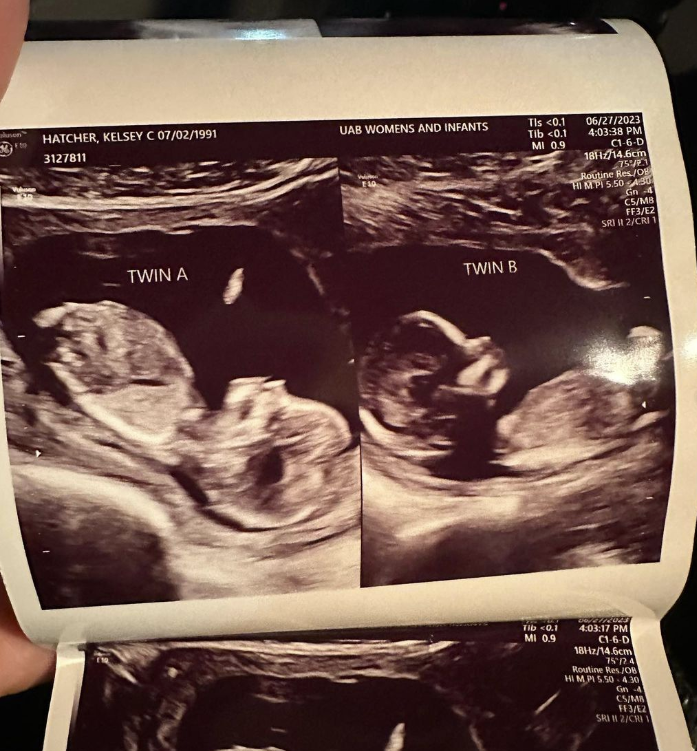

Kelsey Hatcher ist ein medizinisches Wunder. Die Amerikanerin verfügt über zwei Gebärmütter, jede mit einem eigenen Gebärmutterhals, ein Zustand, der bei weniger als einem Prozent der Frauen vorkommt. In jeder ihrer Gebärmütter wächst ein Mädchen heran, was diese Schwangerschaft zu einer medizinischen Sensation macht. Die Mädchen, die um Weihnachten herum erwartet werden, sind streng genommen keine Zwillinge, da sie in getrennten Gebärmüttern heranwachsen.

Screenshot des zur Verfügung gestellten Ultraschallbildes ©doubleuhatchlings, Kelsey Hatcher